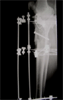

Post

Op

Xrays : alignment maintained with restoration of joint height